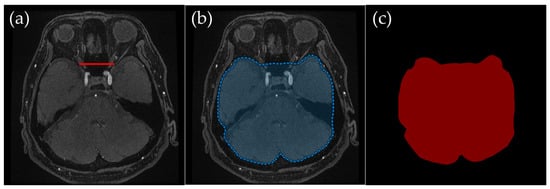

2.3.2. Orbital Level: Excluding Bright Fat Tissue near the Optic Nerves

Orbital Level (Figure 3): An ROI was defined dorsal to the line connecting both optic nerves’ endpoints, thus omitting the orbital region. Bright fat tissue in the orbit can interfere with segmentation due to its high signal intensity in TOF-MRA, leading to potential misclassification as vascular structures. This issue is especially pronounced in elderly patients or those with vascular flow impairments, as a lower flow signal in the arteries can become nearly indistinguishable from bright orbital fat. By removing fat signal contamination, the segmentation process ensures more accurate vessel delineation.

Figure 3. Example of manually annotated training data at the orbital level. (a) Original TOF-MRA axial image (red line indicates the line connecting both optic nerves’ endpoints). (b) Manually defined region of interest (ROI) in blue, excluding the external carotid artery and non-intracranial structures. (c) Corresponding indexPNG mask for semantic segmentation training.